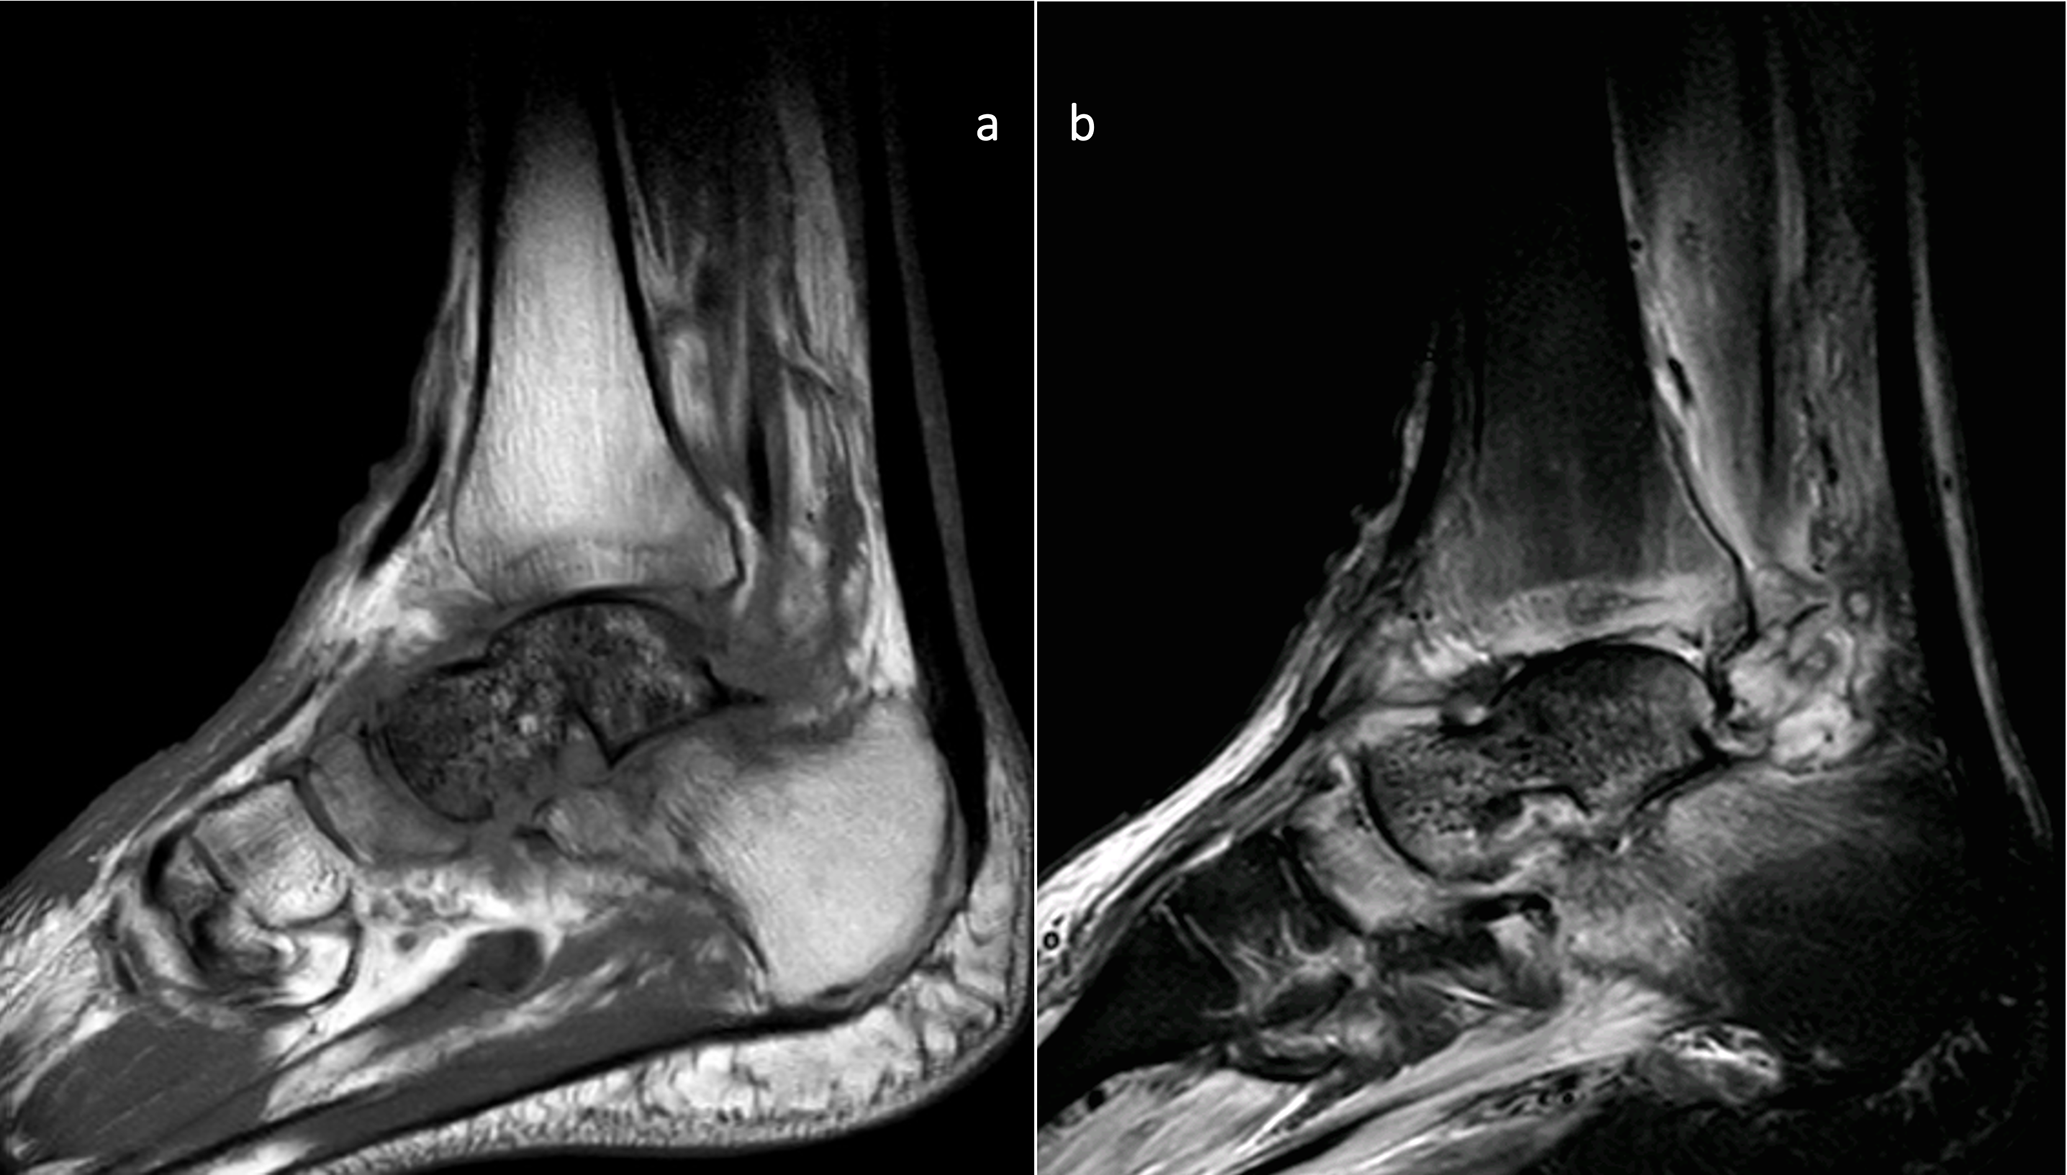

In November 2019, the infection relapsed; at this point, he was referred to our hospital. The flap was in a good condition, with some erythema around it. MRI confirmed AVN and FRI with no other bones involved or purulent collections (Fig. 2).

https://jbji.copernicus.org/articles/10/419/2025/jbji-10-419-2025-f02

Figure 2MRI images of the preoperative state of the talus. Sagittal MRI images showing signs of avascular necrosis and osteomyelitis: (a) T1 and (b) STIR images.